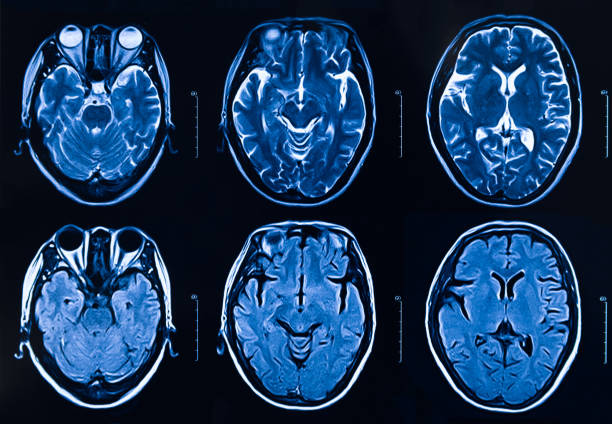

뇌졸중은 뇌경색인지 뇌출혈인지에 따라 판단 역시 다르게 나타납니다. 뇌줄중 환자의 열 명 중 여덟 명은 뇌경색을 가지고 있으며 심장에서 혈액 이동을 막는 혈전이 생기기 때문에 뇌에도 원활한 혈액 공급이 되지 않아 뇌혈관이 막히며 문제가 발생하며 뇌출혈은 열 명 중 두 명꼴로 나타나는데 뇌 신경 손상만 있는 것이 아니라 혈액이 뇌 속에 고여 조직을 압박하거나 충격을 주기도 하는데 결국 혈액을 운반하는 혈관 건강이 좋지 않아지면서 나타나는 뇌졸중 역시 서구화된 식습관과 생활습관으로 고지혈증과 같은 심혈관계 질환으로 동맥경화가 유발되며 나타나고 있어 주의가 요구됩니다.